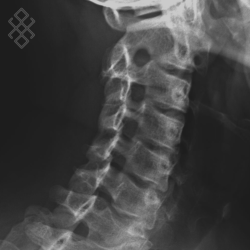

Radiographie du Rachis cervical

La durée de l'examen est d'environ 5 minutes. Durant les clichés radiographiques, vous serez positionné entre la plaque contenant le film et le tube du rayons X. Il vous sera aussi demandé d'ouvrir et de fermer la bouche à plusieurs reprises pour que les articulations puissent être étudiées de manière dynamique.